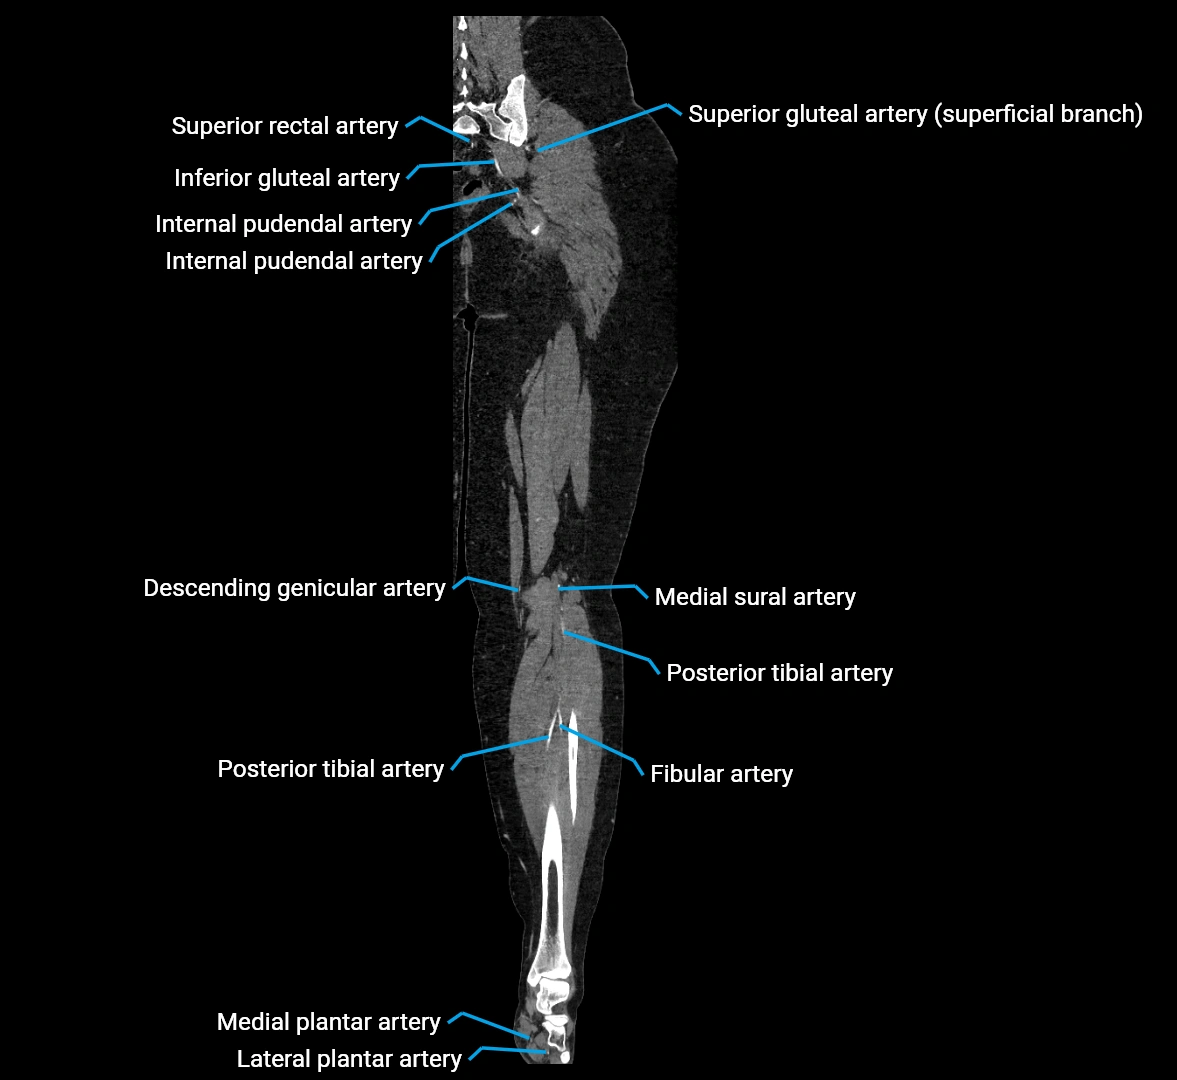

CT images

image